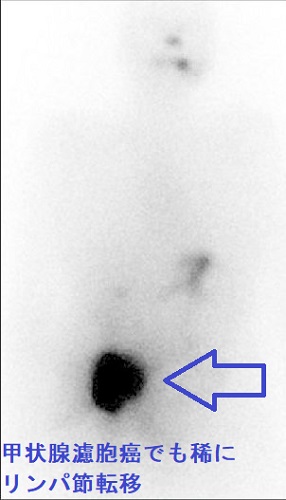

甲状腺濾胞癌の局所再発

甲状腺濾胞癌の局所再発は、切除手術での遺残だけでなく、甲状腺穿刺細胞診後再発(穿刺経路再発)もあります。また、稀ながらリンパ節転移・リンパ節再発する場合もあります。甲状腺濾胞癌の特殊型 甲状腺濾胞癌(好酸性細胞型、膨大細胞癌)ではリンパ節転移・リンパ節再発が主です。

リンパ節転移・リンパ節再発

甲状腺濾胞癌血行性転移なので、リンパ節転移しないと言うのは間違いです。甲状腺乳頭癌と比較すれば極めて少ないですが、元々、甲状腺濾胞細胞から発生した癌である以上、リンパ節転移はあり得ます。そして、甲状腺濾胞癌手術時のリンパ節郭清の有無が、その後の死亡率を左右すると言う報告もあります(World J Surg. 2002 Aug;26(8):1017-22.)。

(左)I-131 シンチグラフィーでは、鼠径部リンパ節転移を認めた。(右)その細胞診(Indian J Endocrinol Metab. 2013 Mar;17(2):353-4)

甲状腺濾胞癌でもリンパ節転移 131Iシンチグラフィー